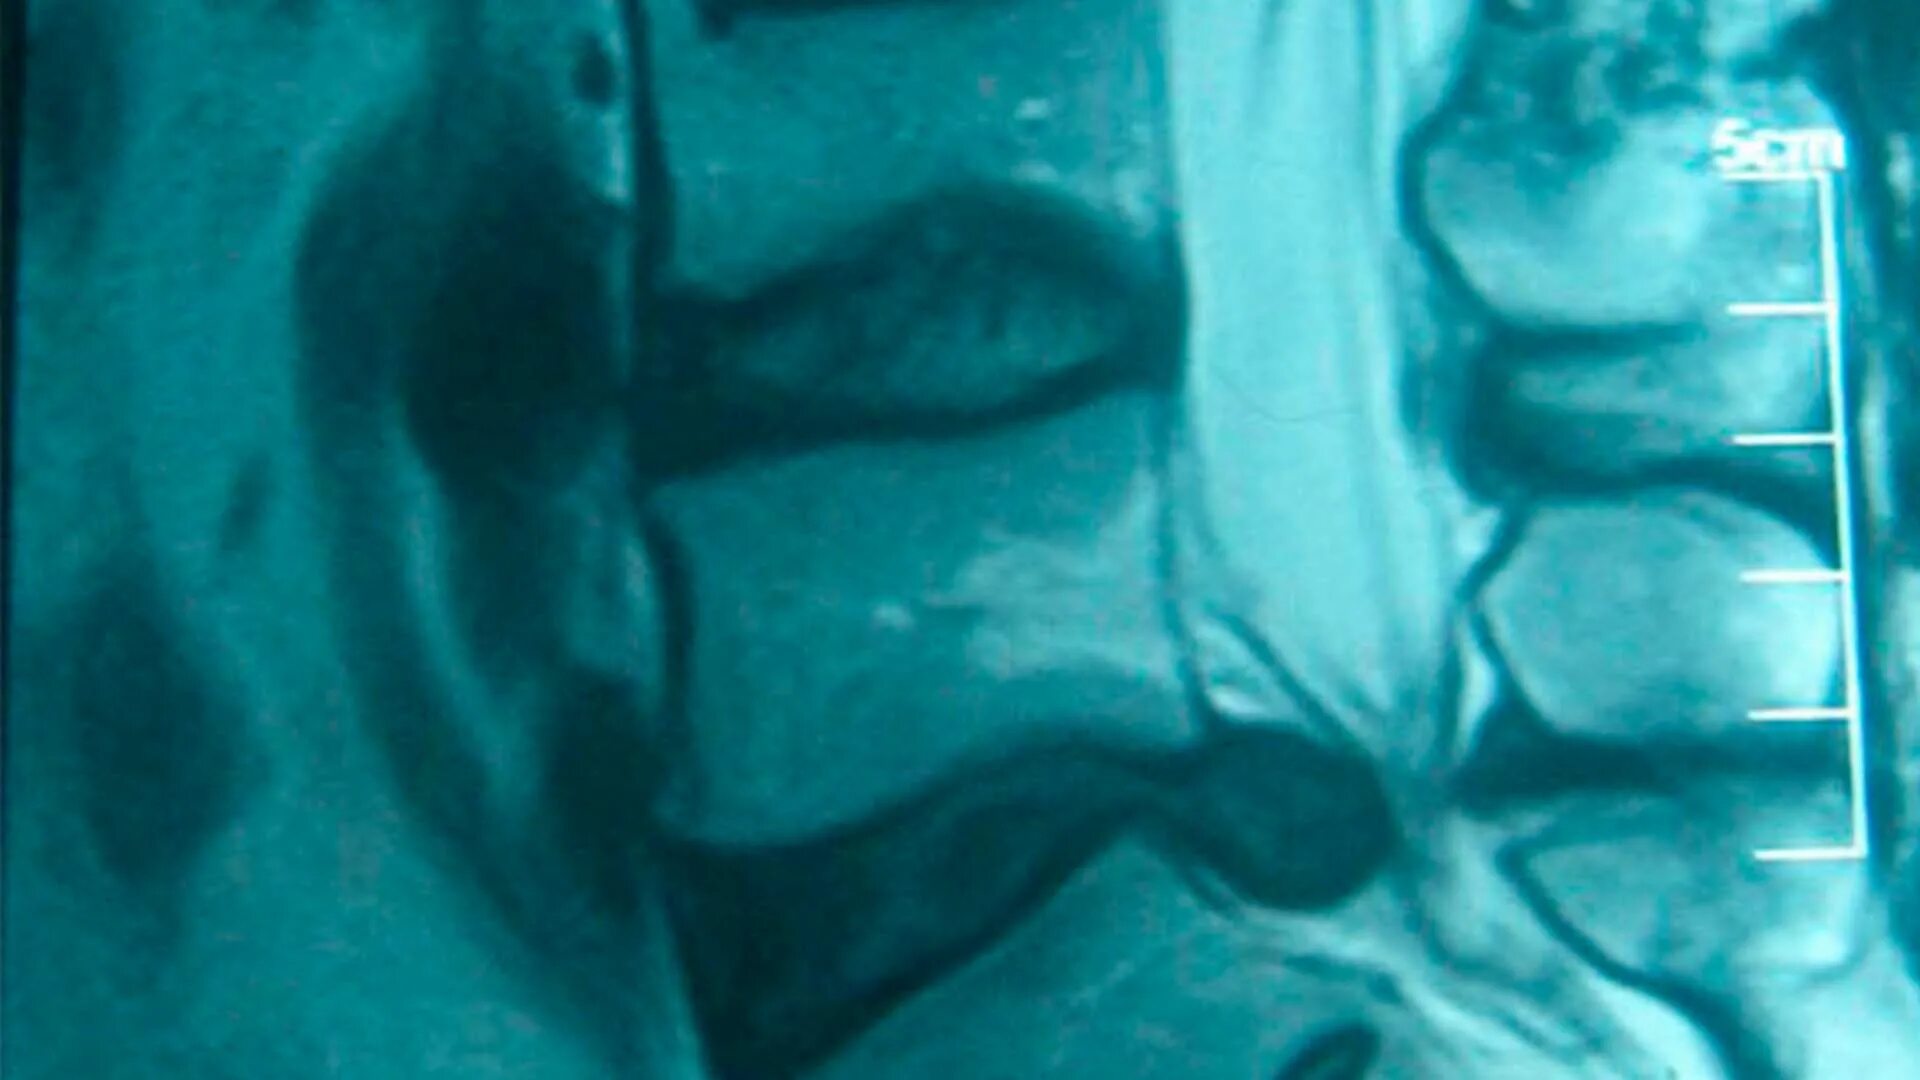

Грыжа шейного мкб